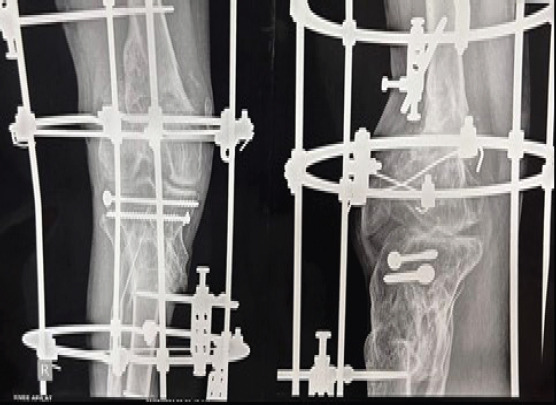

Case report: We present the case of 48-year-old male with non-union of proximal tibia and distal femur fracture with Ilizarov in situ. A floating knee on the right side was unsuitable for open reduction and internal fixation due to poor skin health. Ilizarov fixation was planned for the patient. This instance demonstrates the difficulties associated with floating knee. The technique's limits in treating specific periarticular fractures are highlighted by the Ilizarov fixation's failure in this instance.